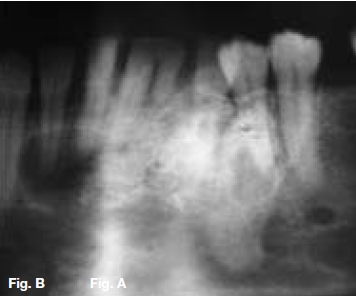

A 30-year old female presented with a swelling extending between 35 and 43, which had grown over the past ten months (Figs.A,B,C), with intermittent pain. Figures D,E,F show a similar case in a 15 year old male patient. Describe the radiological features and list your differential diagnosis.

The cropped pantomograph (Fig.B) shows a multilocular radiolucency of an expansive tumour containing varying calcifications. Figures D&E show a well demarcated multilocular lesion in the body/ramus region of the left mandible, with two displaced molar teeth, resorption of the roots of 34 and 35 and tooth-like calcifications at the borders of the lesion. The coronal T2 MRI image (Fig.F) shows a multilocular hyper-intense lesion, with no discernible calcifications. Diagnosis: the rare tumour, odonto-ameloblastoma (OA), first reported by Kemper and Root (1944). Shafer ef al (1983) described this as an odontogenic neoplasm of mixed tissue origin, consistent with both ameloblastoma and odontoma. Histologically, a typical ameloblastoma component whilst the odontoma element may be either compound or complex. Shafer et al (1983) emphasized that this is one neoplastic process with relatively highly undifferentiated tissues. Occurring most commonly in the second decade of life, it may vary in size. Smaller lesions occur between the teeth, confined to the alveolar bone between the crest of the ridge and the teeth apices (Figs. A,B&C). Buccal expansion of the cortex is common, even for smaller lesions. The odontoma component presents various stages of development, early lesions being radiolucent with radiopaque flecks. More mature lesions are better developed odontoma, resembling teeth or as a nonspecific complex odontoma mass. Importantly, this is an aggressive tumour, treated precisely as an ameloblastoma. The differential diagnosis should include: ameloblastic fibro-odontoma, Pinborg tumour, calcifying odontogenic cyst and adenomatoid odontogenic tumour.